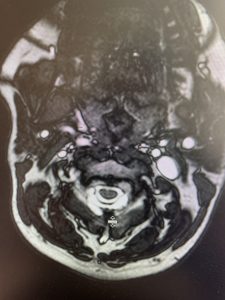

This 57 year-old male presents with severe neck, left shoulder and arm pain and weakness in his hand since being involved in a motor vehicle accident nine months prior. The patient had subsequent left shoulder surgery although he still complained of pain postoperatively and his weakness persisted. He was on no blood thinners. He underwent imaging. The cervical spine MRI revealed an extensive dorsal epidural collection from C1-2 through C5 with associated spinal cord compression. In addition there were multisegmental degenerative changes with foraminal stenosis worse at C4-5 (Fig. 1a and 1b).

(1a) Sagittal and axial T2-weighted cervical MRI demonstrating extensive dorsal epidural collection with hyperintense signal consistent with fluid causing spinal cord compression.

The fluid was possibly consistent with CSF versus chronic hematoma. The patient was also noted to have a high signal within the interspinous space of C3-C4. This high signal was consistent with a ruptured C3-4 interspinous ligament. Cervical flexion-extension x-rays demonstrated 6 mm of widening of the C3-4 interspinous space on flexion x-ray consistent with cervical instability (Fig. 2a and 2b).